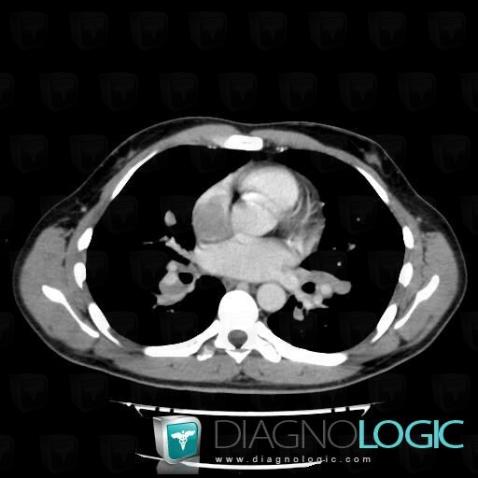

Voici les informations spécifiques à l'image clé ci dessus:

- Diagnostic Lymphome , Localisation(s) Cavités cardiaques / Péricarde, comportant les gammes

Voici les informations spécifiques à l'image clé ci dessus:

- Diagnostic Lymphome , Localisation(s) Cavités cardiaques / Péricarde, comportant les gammes